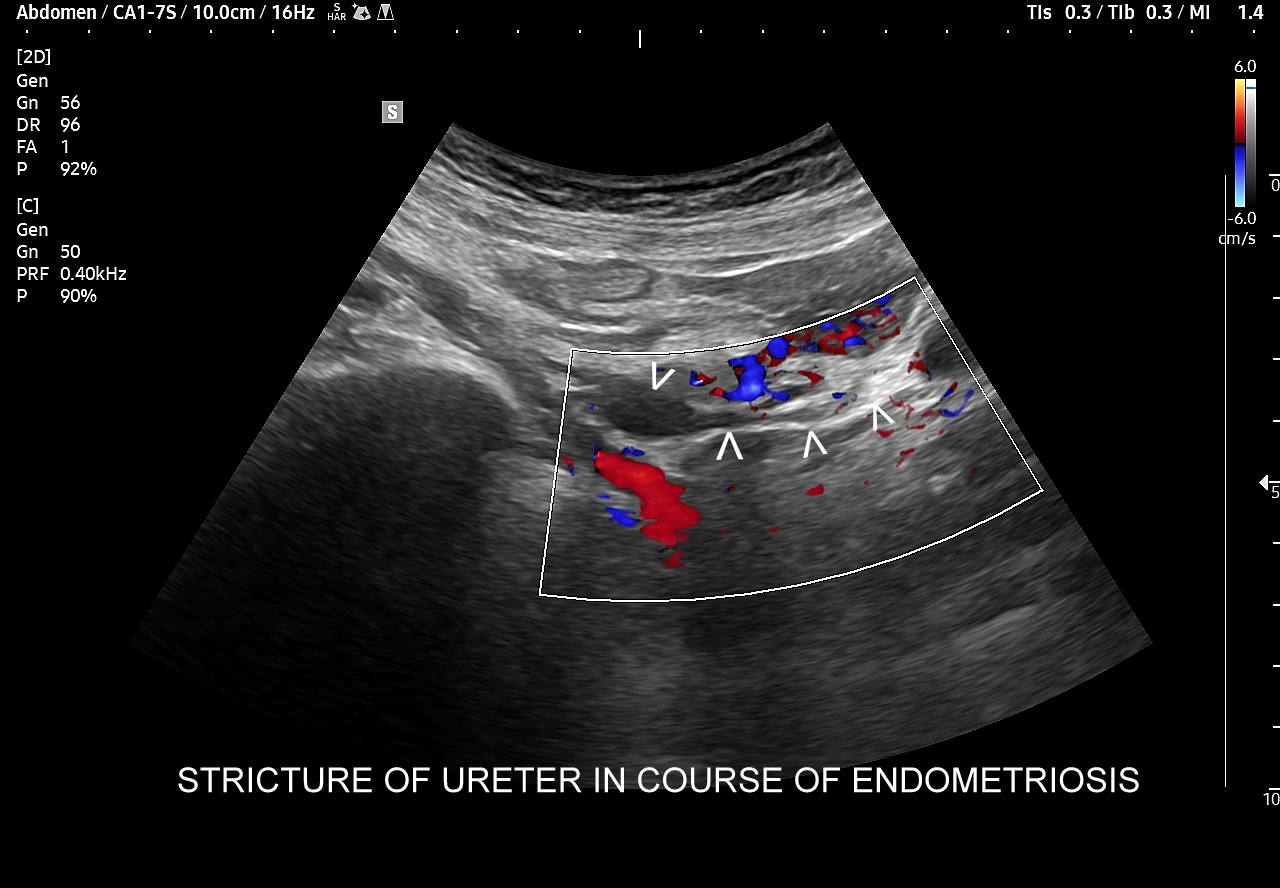

W badaniu USG ogniska endometriozy zwykle przyjmują formę hypoechogennych guzków i nieregularnych mas; mogą być niejednorodne echogenicznie i zawierać drobne obszary torbielowate; w trybie color-Doppler i MVI wykazują skąpe unaczynienie.

Na skanach w niniejszym artykule zaprezentowany jest przypadek endometriozy głębokiej w miednicy mniejszej z intraluminalnym nacieczeniem dystalnego odcinka moczowodu, jego całkowitą niedrożnością i wtórnym wodonerczem. Choroba w tak zaawansowanym stadium wykryta została przypadkowo w rutynowym przezbrzusznym badaniu USG jamy brzusznej. W ramach diagnostyki różnicowej przeprowadzone zostały badanie CT, MRI oraz ureterocystoskopia z pobraniem materiału do badania histopatologicznego, na podstawie którego postawiono rozpoznanie endometriozy.